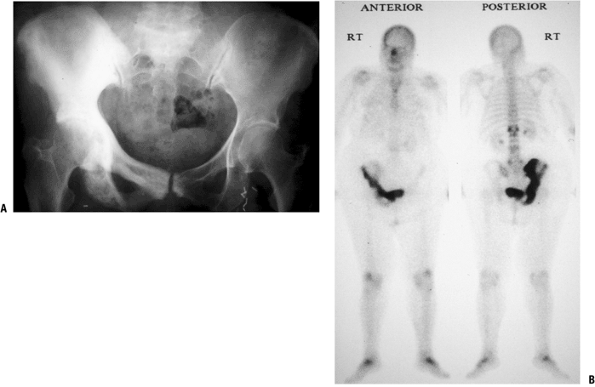

the bones.P.238 Figure 8-9 Figure 8-9

An isolated left proximal femoral bone lesion shows a permeative lytic

process involving the proximal femur with confluent uptake on bone scan

involving the femoral epiphysis, metaphysis, and proximal diaphysis.

Biopsy showed lymphoma.![]() Figure 8-10 Figure 8-10

Paget’s disease of bone in its sclerotic phase can be confused with

prostate cancer. This patient with Paget’s disease of the entire right

hemipelvis shows the typical coarsening of trabeculae and bony

expansion (both best seen in the pubic rami) as well as confluent

uptake on the bone scan.P.239Table 8-5 Laboratory Tests Important in The Evaluation of Metastatic DiseaseLaboratory Test Positive Finding Disease Association Serum protein electrophoresis Monoclonal spike (monoclonal gammopathy) Multiple myeloma Urine protein electrophoresis Bence Jones proteins Multiple myeloma Lactate dehydrogenase Elevated Lymphoma (nonspecific; depends on disease load; also with osteogenic sarcoma, Ewing sarcoma) Prostate specific antigen Elevated Prostate carcinoma Urinalysis Hematuria Renal cell carcinoma Alkaline phosphatase Elevated Paget’s disease of bone (nonspecific; also with osteogenic sarcoma)